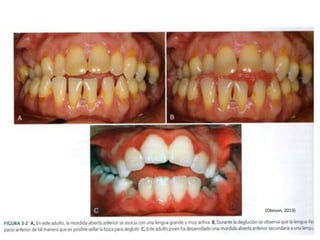

MORDIDA CRUZADA La oclusiónde los dientes se realiza de tal forma que las cúspides bucales maxilares entran en contacto con el área de la Fosa Central de los dientes mandibulares. (Puede ser consecuencia de la diferencia de tamaños de arcadas Oseas o erupcion dentaria). (Okeson, 2013)